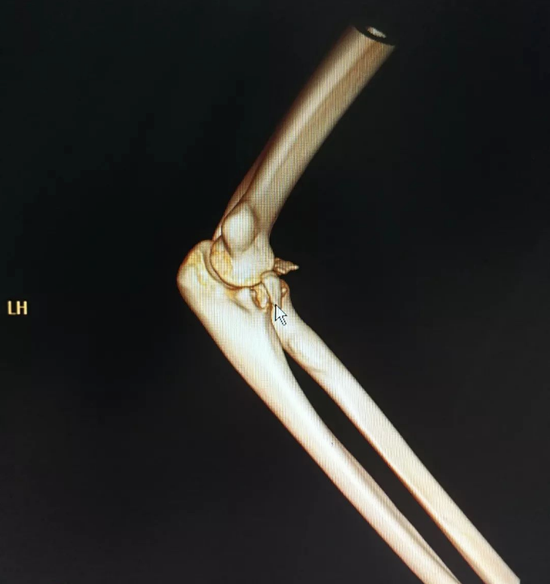

20日中午,20岁的年轻小伙李帅(化名)托着右手走进武汉市第四医院骨科急诊室,医生黄振峰一眼就看到李帅右手肘严重畸形,初步判断李帅的手臂应该发生了骨折。经过进一步CT检查,果然发现患者右手肘骨折伴脱位。

目前,患者伤情比较严重,除了骨折,韧带也受伤了,在进行复位后,后期还需要接受手术治疗。